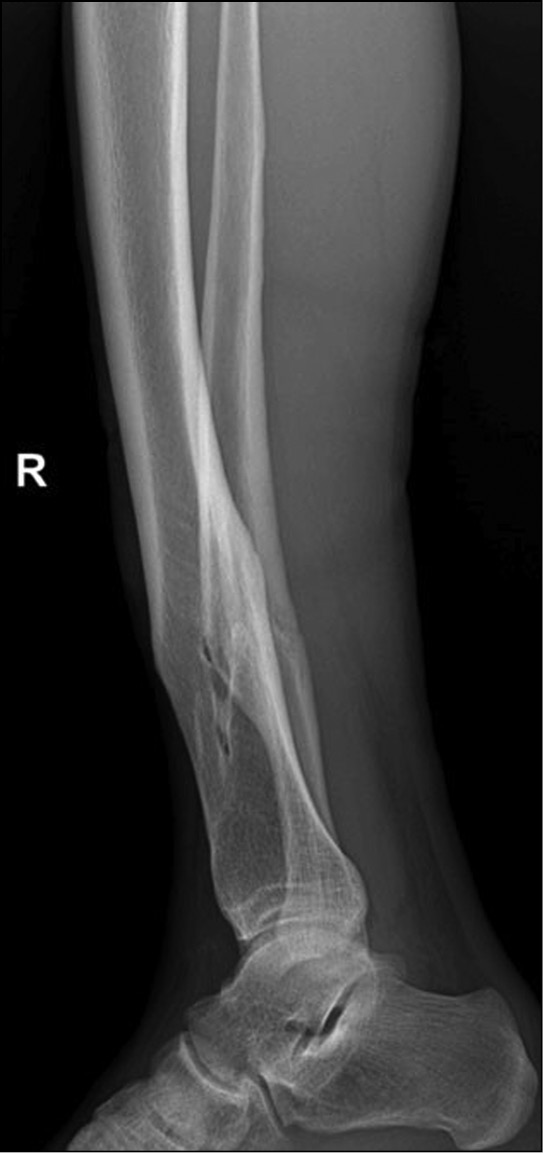

Результаты рентгенологического обследования от 20.07.2021. Судебно-медицинским экспертом изучены две цифровые рентгенограммы в электронном виде на компакт-диске на имя Р., 1987 года рождения: на рентгенограммах средней-нижней трети правой голени с захватом голеностопного сустава в прямой и боковой проекциях «свежих» костно-травматических изменений не выявлено. Определяется старый сросшийся перелом нижней трети диафиза большеберцовой кости и аналогичный старый перелом нижней трети диафиза малоберцовой кости (на одном уровне с переломом большеберцовой кости) с хорошо выраженной, плотной костной мозолью, признаками перестройки костной ткани. Линии переломов не просматриваются, имеют место выраженная посттравматическая деформация диафизов, истончение и деформация кортикального слоя в проекции сформированной костной мозоли (рис. 1, 2).

Рис. 2. Рентгенограмма костей правой голени в боковой проекции. Старые сросшиеся переломы нижней трети диафизов берцовых костей.

В ходе исследования судмедэкспертом рентгенограмм гр. Р. установлены и описаны несомненные признаки консолидированного перелома берцовых костей, давностью от одного года и более, с признаками хронического посттравматического остеомиелита большеберцовой кости. Изучение представленных рентгенограмм позволило эксперту прийти к выводу, что данные переломы не имеют отношения к вышеописанным событиям от 20.07.2021, поэтому судебно-медицинской оценке не подлежат.